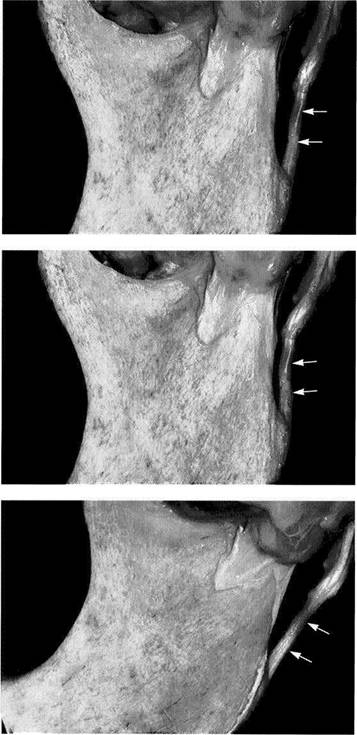

BilaminarZone

The posterior portion of the temporomandibular joint has been variously referred to as the bilaminar zone (Rees 1954), retroarticular plastic pad (Zenker 1956), retroarticu-lar pad (DuBrul 1988), retrodiskal fat pad (Murikami and Hoshino 1982), or trilaminar zone (Smeele 1988). It consists of an upper layer (superior stratum) and a lower layer (inferior stratum) (Rees 1954, Griffin and Sharpe 1962). Between these two layers lies the genu vasculosum with its numerous vessels, nerves, and fat cells (Griffin and Sharpe 1962). The superior stratum is composed of a loose network of elastic and collagen fibers, fat, and blood vessels (Zenker 1956).

By contrast, the inferior stratum is made up of tight collagen fibers (Rees 1954, Wilkes 1978, Luder and Bobst 1991). In the bilaminar zone the collagen fibers are more loosely organized and run more or less in the sagittal plane (Mills et al. 1994b). The fibers of both strata stream into the pars posterior of the disk and there intertwine with the transverse fibers of the pars posterior and the sagittal fibers of the pars intermedia (Scapino 1983). The elastic fibers in the bilaminar zone have larger diameters than those of the disk and are concentrated predominantly in the superior stratum (Rees 1954, Scapino 1983, Mills et al. 1994a).

|

Macroscopic

anatomical

preparation

Left: With the jaws closed the bil-aminar zone (1) fills the space posterior to both the pars posterior (2) and the condyle (3). The inferior stratum stabilizes the disk on the condyle in the sagittal plane. An overextension of the bilaminar zone through posterosuperior displacement of the condyle is an essential precondition for an anterior disk displacement to occur. Right: With the mouth open the genu vasculosum (1) fills with blood. The superior stratum (2) and inferior stratum (3) can be easily identified.

Variants

of the postero

superior attachment

Left: Type A insertion. The superior stratum and the posterior joint capsule run separately to their insertions in the fissures. This type of insertion occurs most often in the medial portion of the joint.

Right: Type B insertion. Here the superior stratum and the posterior joint capsule merge before reaching the fissures and continue posterosuperiorly as one uniform, undifferentiated structure. This variant is the second most common in the medial portion of the joint.

Left: Type C insertion. The superior stratum inserts on the glenoid process because the fissures are completely filled by the posterior portion of the joint capsule. This type of insertion is found most frequently in the lateral part of the joint.

Right: Type D insertion. In this rare variant no posterior capsule structure can be demonstrated histologically. The posterior boundary is formed by the parotid fascia.

The superior stratum is attached posteriorly to

the bony auditory meatus,

the cartilaginous part of the auditory meatus, and the fascia of the parotid gland (Scapino 1983). Four insertion variations can be distinguished (Bumann

et al.

The inferior stratum inserts on the posterior side of the condyle below the fibrocartilaginous articulating surface and is responsible for stabilizing the disk on the condyle. Anterior disk displacement is possible only when the predominantly collagenous inferior stratum becomes overstretched. The superior stratum, on the other hand, is responsible for retracting the articular disk, especially dur-

ing the initial phase of closure, but is of lesser importance in the occurrence of anterior disk displacement (Eriksson et al. 1992). These facts are very important to consider in the diagnosis and treatment of disk displacements. Continuous posterior or posterosuperior loading of the bilaminar zone eventually leads to fibrosis and sometimes to the formation of a pseudodisk (Hall et al. 1984, Isberg et al. 1986, Kurita et al. 1989, Westesson and Paesani 1993, Bjornland and Refsum 1994).

Histology of the trilaminar

zone

The superior stratum (1), genu vas-culosum (2), and inferior stratum (3) can be clearly distinguished from one another. Sensory and sympathetic nerve fibers provide pain perception and regulation of blood-vessel tonus. Here the neuropeptides A and Y effect vasoconstriction (Lundberg et al. 1990, Grundemar and Hakanson 1993) while vasodilation is brought about by the vasoactive intestinal peptide, the peptide histidine-isoleucine amide and acetylcholine (Widdicombe1991).

Progressive

adaptation

(fibrosis)

Chronic overloading brings about fibrosis (arrows) and reduction of the number of blood vessels. Such fibrosis can be seen in 64-90% of patients, depending on the position of the disk. Posterior and pos-terosuperior condylar displacement without adaptation of the bilaminar zone is a common cause of joint pains. Therefore, previous adaptation of the bilaminar zone can be considered a favorable factor for treatment.

Function

and structural

adaptation of the bilaminar zone

In addition to supplying nutrients and proprioception, the inferior stratum is of special importance in stabilizing the disk in the sagittal plane. Increased functional loading can lead to its fibrosing. Our own studies indicate that in spite of mechanical loading, fibrosis does not occur in 10-36% of joints. Chronic nonphysiological overloading usually results in perforation, overexte-nion. or inflammation.